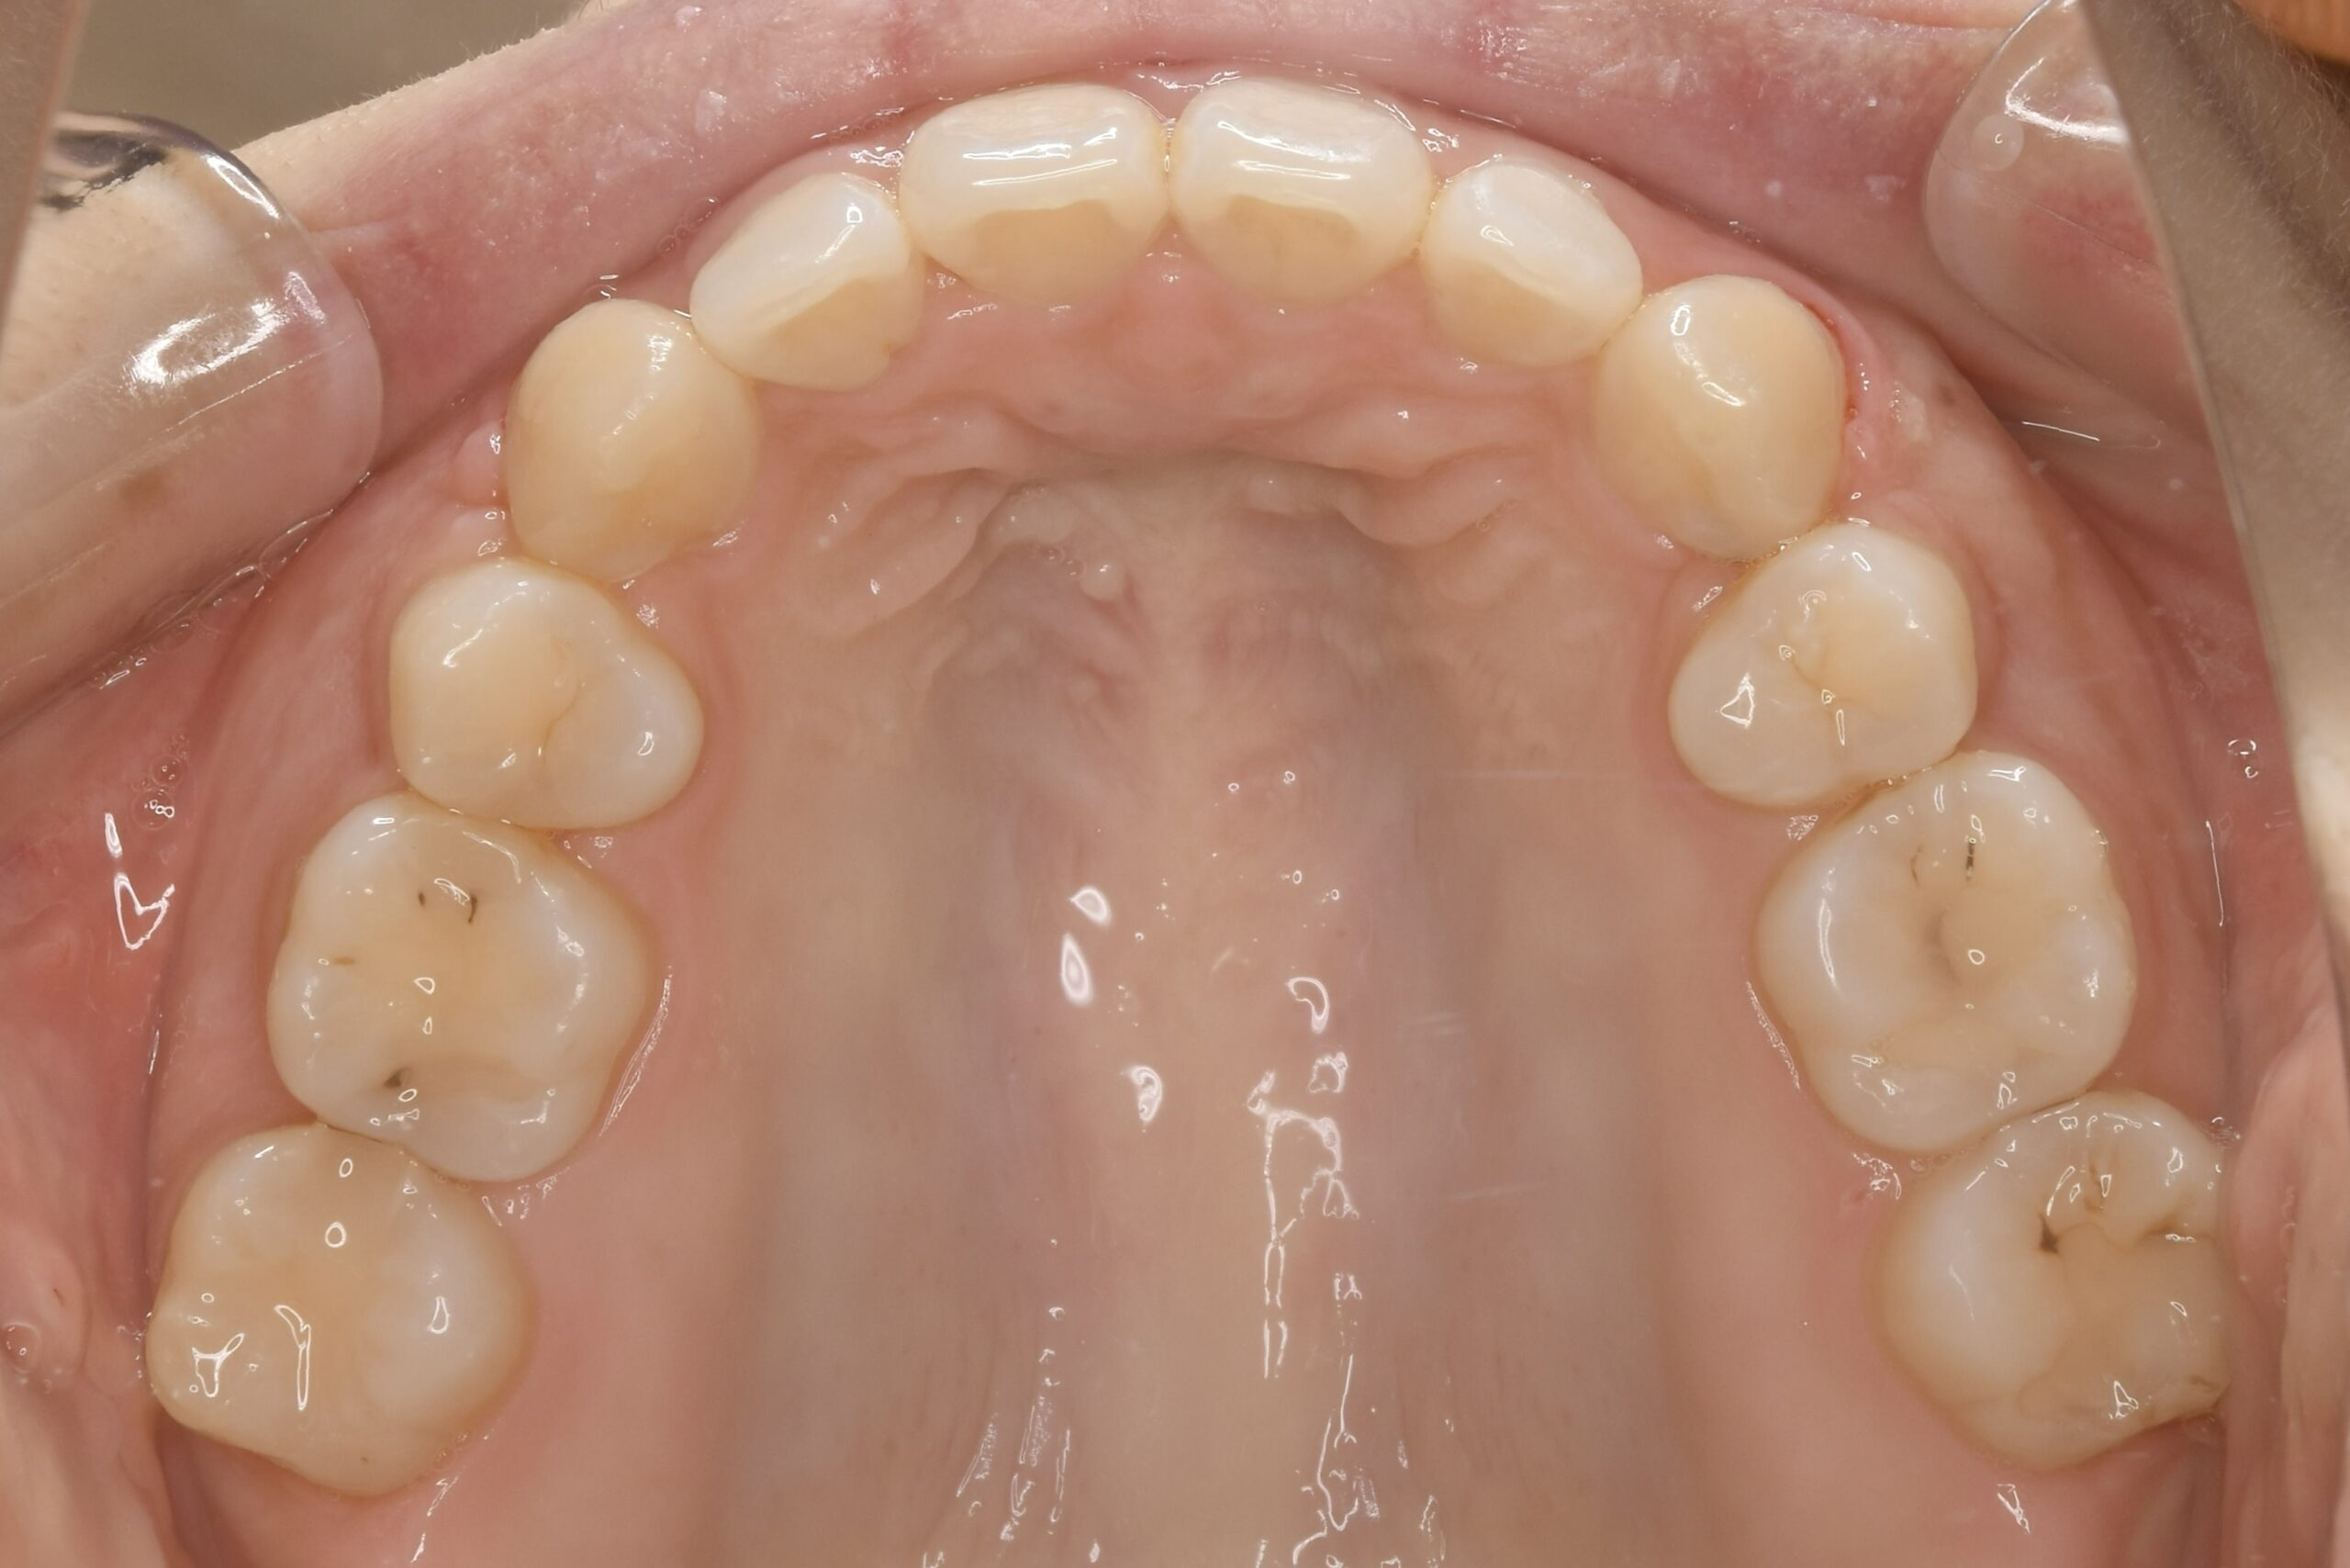

32歳 女性 治療期間:1年7ヶ月

AFTER

診断名・主な症状 叢生を伴う上顎前突

治療内容 上下とも歯を2本抜いて、上の前歯を後方に引きながら、でこぼこを治しました。

使用装置 マウスピース矯正装置(インビザライン)

抜歯部位 上 両側4番目

下 右側4番目、左側5番目

治療期間 1年7ヶ月